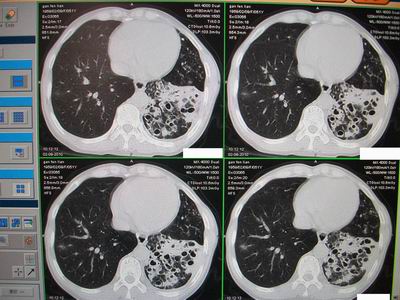

标题: CT24546:支气管扩张?多发性肺囊肿?请高手发表意见吧 [打印本页]

标题: CT24546:支气管扩张?多发性肺囊肿?请高手发表意见吧

临床:女性,51岁,一年来咳嗽、咳痰,反复发作,近两个月带少许血丝。

查体:精神较差,消瘦,余未见明显异常。

图片如下:\

“印戒征”,支扩伴感染

病变主要延肺动脉走形,多发囊状影较小且壁厚,还得先考虑---支扩伴感染。

支扩:腔小、壁厚、多液平;多发性肺囊肿:腔大、壁薄、少液平,本例符合支扩合并感染